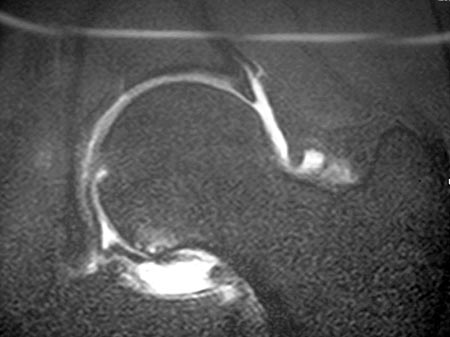

Todos los pacientes fueron estudiados con radiografías en posición de frente y “Cross table”, Tomografía Axial Computada, Resonancia Magnética Nuclear y Artroresonancia (Fig. 5 y 6).

Figura 5: Artroresonancia, corte axial. Lesión del Labrum./ Figura 6: Artroresonancia, corte coronal. Lesión del Labrum.